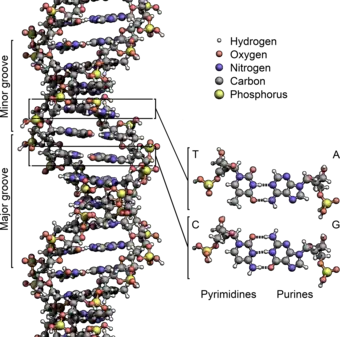

- ... vinca alkaloids are chemotherapy drugs that inhibit the polymerization of tubulin, whereas taxanes are produced by plants of the genus Taxus that inhibit tubulin depolymerization?